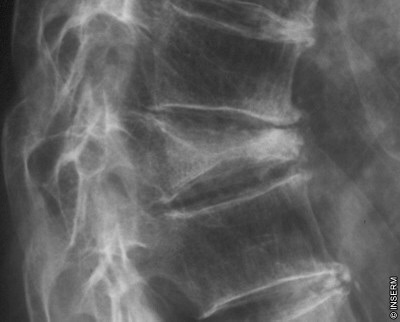

Ronéo 8 page 5 touuut en bas, il est écrit : "la partie antérieure des corps vertébraux présente donc une faiblesse à l'origine des tassements vertébraux (accompagnés souvent par l'arthrose). Ce tassement est cunéiforme à base postérieure" ne serait-ce point à base antérieure ?